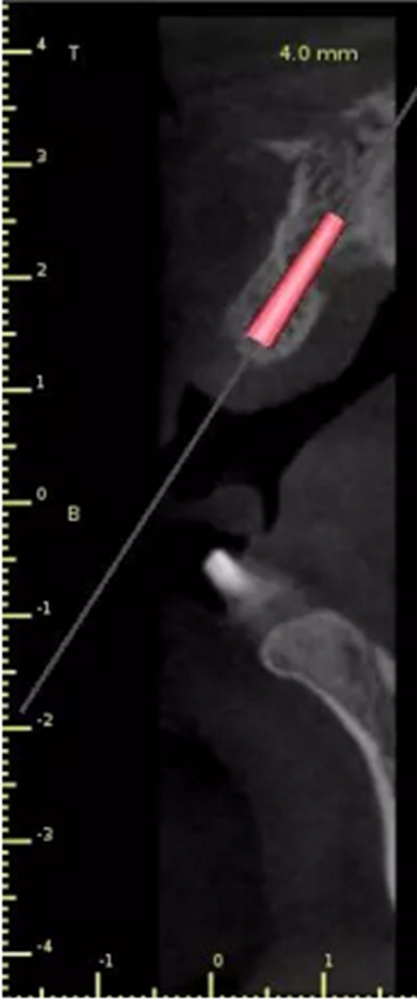

2.術(shù)前植體設(shè)計(jì)

3.術(shù)前導(dǎo)板設(shè)計(jì)

頜面部消毒→鋪襟→局麻下翻瓣→帶入導(dǎo)板→定位鉆定位→擴(kuò)孔鉆擴(kuò)孔→植入3.0x13植體→覆蓋螺絲→縫合→沖洗→術(shù)后醫(yī)囑